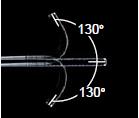

130°上/下角度,便于插入和诊断

宽角范围允许平滑插入和更容易操纵性,彻底检查喉和下咽

弯曲部分 | 角度范围 | 上/下 130° |